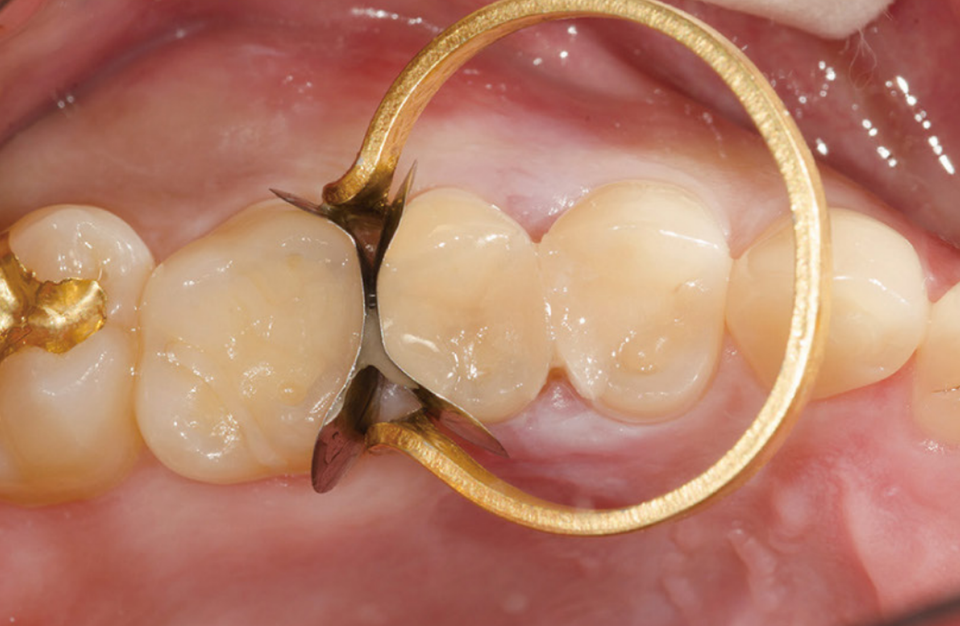

#14~#16 레진 충전

왜 이런 과정을 사진으로 기록할까? 개원한 치과의사는 누구의 간섭도 받지 않고 자신의 양심과 임상능력을 따라 진료한다. 임상 과정을 사진으로 기록하고 정리하는 과정에서 자신의 부족한 점이 드러난다. 최종 치료결과가 좋을 때는 자신감과 직업적인 보람을 얻기도 한다.